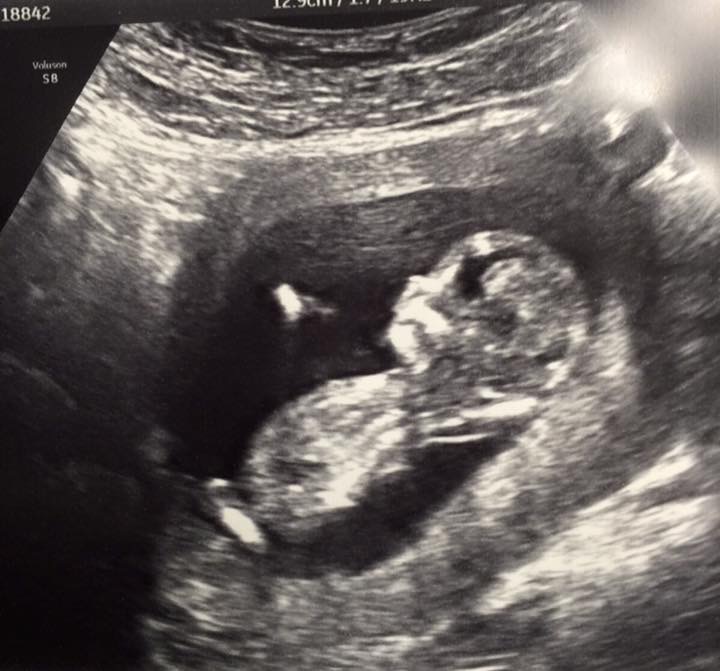

Attachment 28478 Any guesses anyone on the gender many thanks

no visible nub, sorry. More pics?

Can't see, good luck Hun